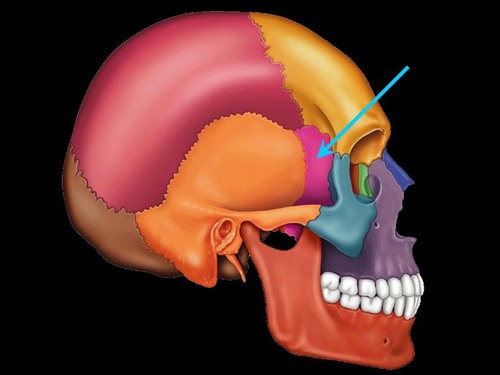

coronal suture